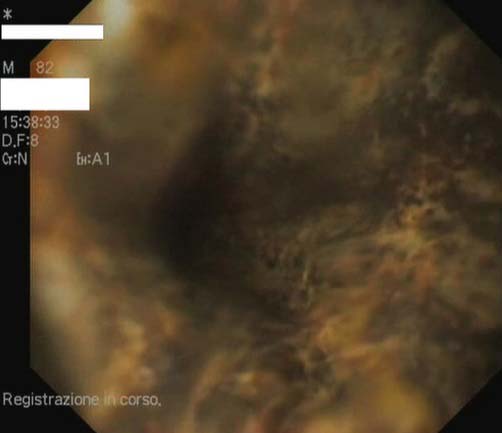

이탈리아 나폴리 페데리코 2세 대학교 의대 연구진은 82세 남성 A씨가 이틀 동안 커피 찌꺼기가 섞인 구토를 한다며 입원했다고 밝혔다. A씨는 관상동맥질환, 고혈압, 당뇨를 앓고 있었다. 식도위장십이지장 내시경 검사를 해봤더니 식도 전체에 퍼진 검은색 점막이 보였다. 의료진은 양성자 펌프 억제제(위산 분비를 억제하는 약물의 일종) 등을 써서 치료했다고 밝혔다. 이 사례는 '임상사례보고저널'에 게재됐다.